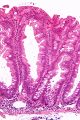

Sessile serrated adenoma 3 very high mag.jpg

صورة مجهرية لورم غدي مشرشر مفلح.

تشخص الأورام الغدية المشرشرة المفلطحة بظهورها المجهري؛ هستولوجياً، تتميز (1) بالتمدد القاعدي للخبايا، (2) تشرشر الخبايا القاعدية، (3) الخبايا الممتدة أفقياً حتى الغشاء القاعدي (الخبايا الأفقية)، و(4) تفرع الخبايا. أكثر الخصائص هذه الخصائص شيوعاً هو التمدد الجانبي للخبايا.

على عكس الأورام الغدية القولونية التقليدية، (مثل الورم الغدي الأنبوبي، الورم الغدي الزغبي)، ليس لديها (عادة) تغيرات نووية (فرط الانصباغ النووي، الاحتشاد النووي، النوية ذات الشكل البيضاوي/شكل السيجار).